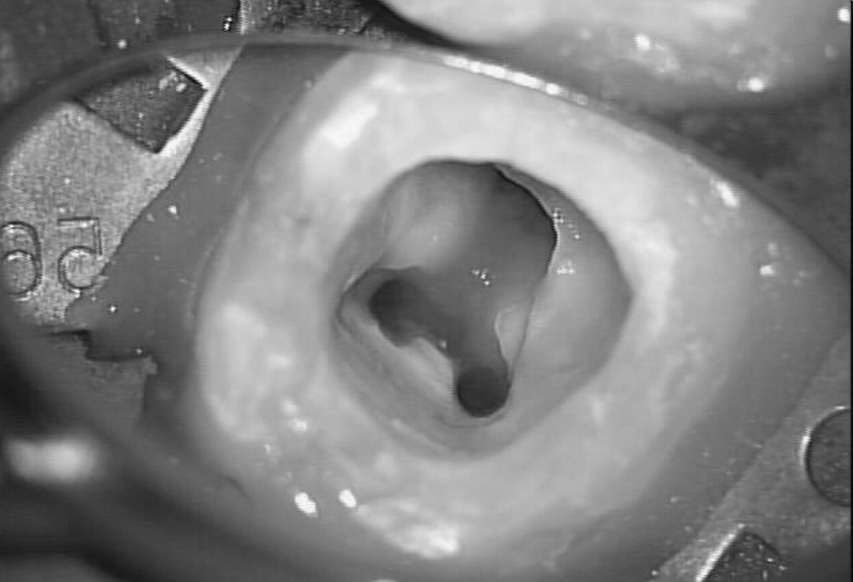

最近ではこの問題を解決する方法があります。それが顕微鏡を用いた治療です。当クリニックの顕微鏡は術野を2倍から34倍に拡大して確認することができ、狭くて暗い部位には顕微鏡から高照度のライトを当てることにより、明るくすることができるようになりました。

明るく拡大することにより治療部位の情報量は数倍になり、的確な診断のもと、取り除かなくてはならない部位と健康な部位の境界が明瞭にできます。今までのように見えていないことで必要以上に削る必要がなくなり、感染して悪くなった部位の適切な除去、歯とぴったり合った適合精度の高い人工歯の作成・装着によって、再治療になる確率を下げることができるようになります。また歯に対して最小の侵襲で処置を行えるようになりました。つまり、1回で治療を終了させて再治療になるリスクを大幅に減らすことができるのです。

5.1倍、8.2倍、13.6倍、21.3倍と、段階的に拡大した状態をお見せします。肉眼では線にしか見えない部分もマイクロスコープで拡大して見ると「NIPPONGINKO」とはっきり見えます。